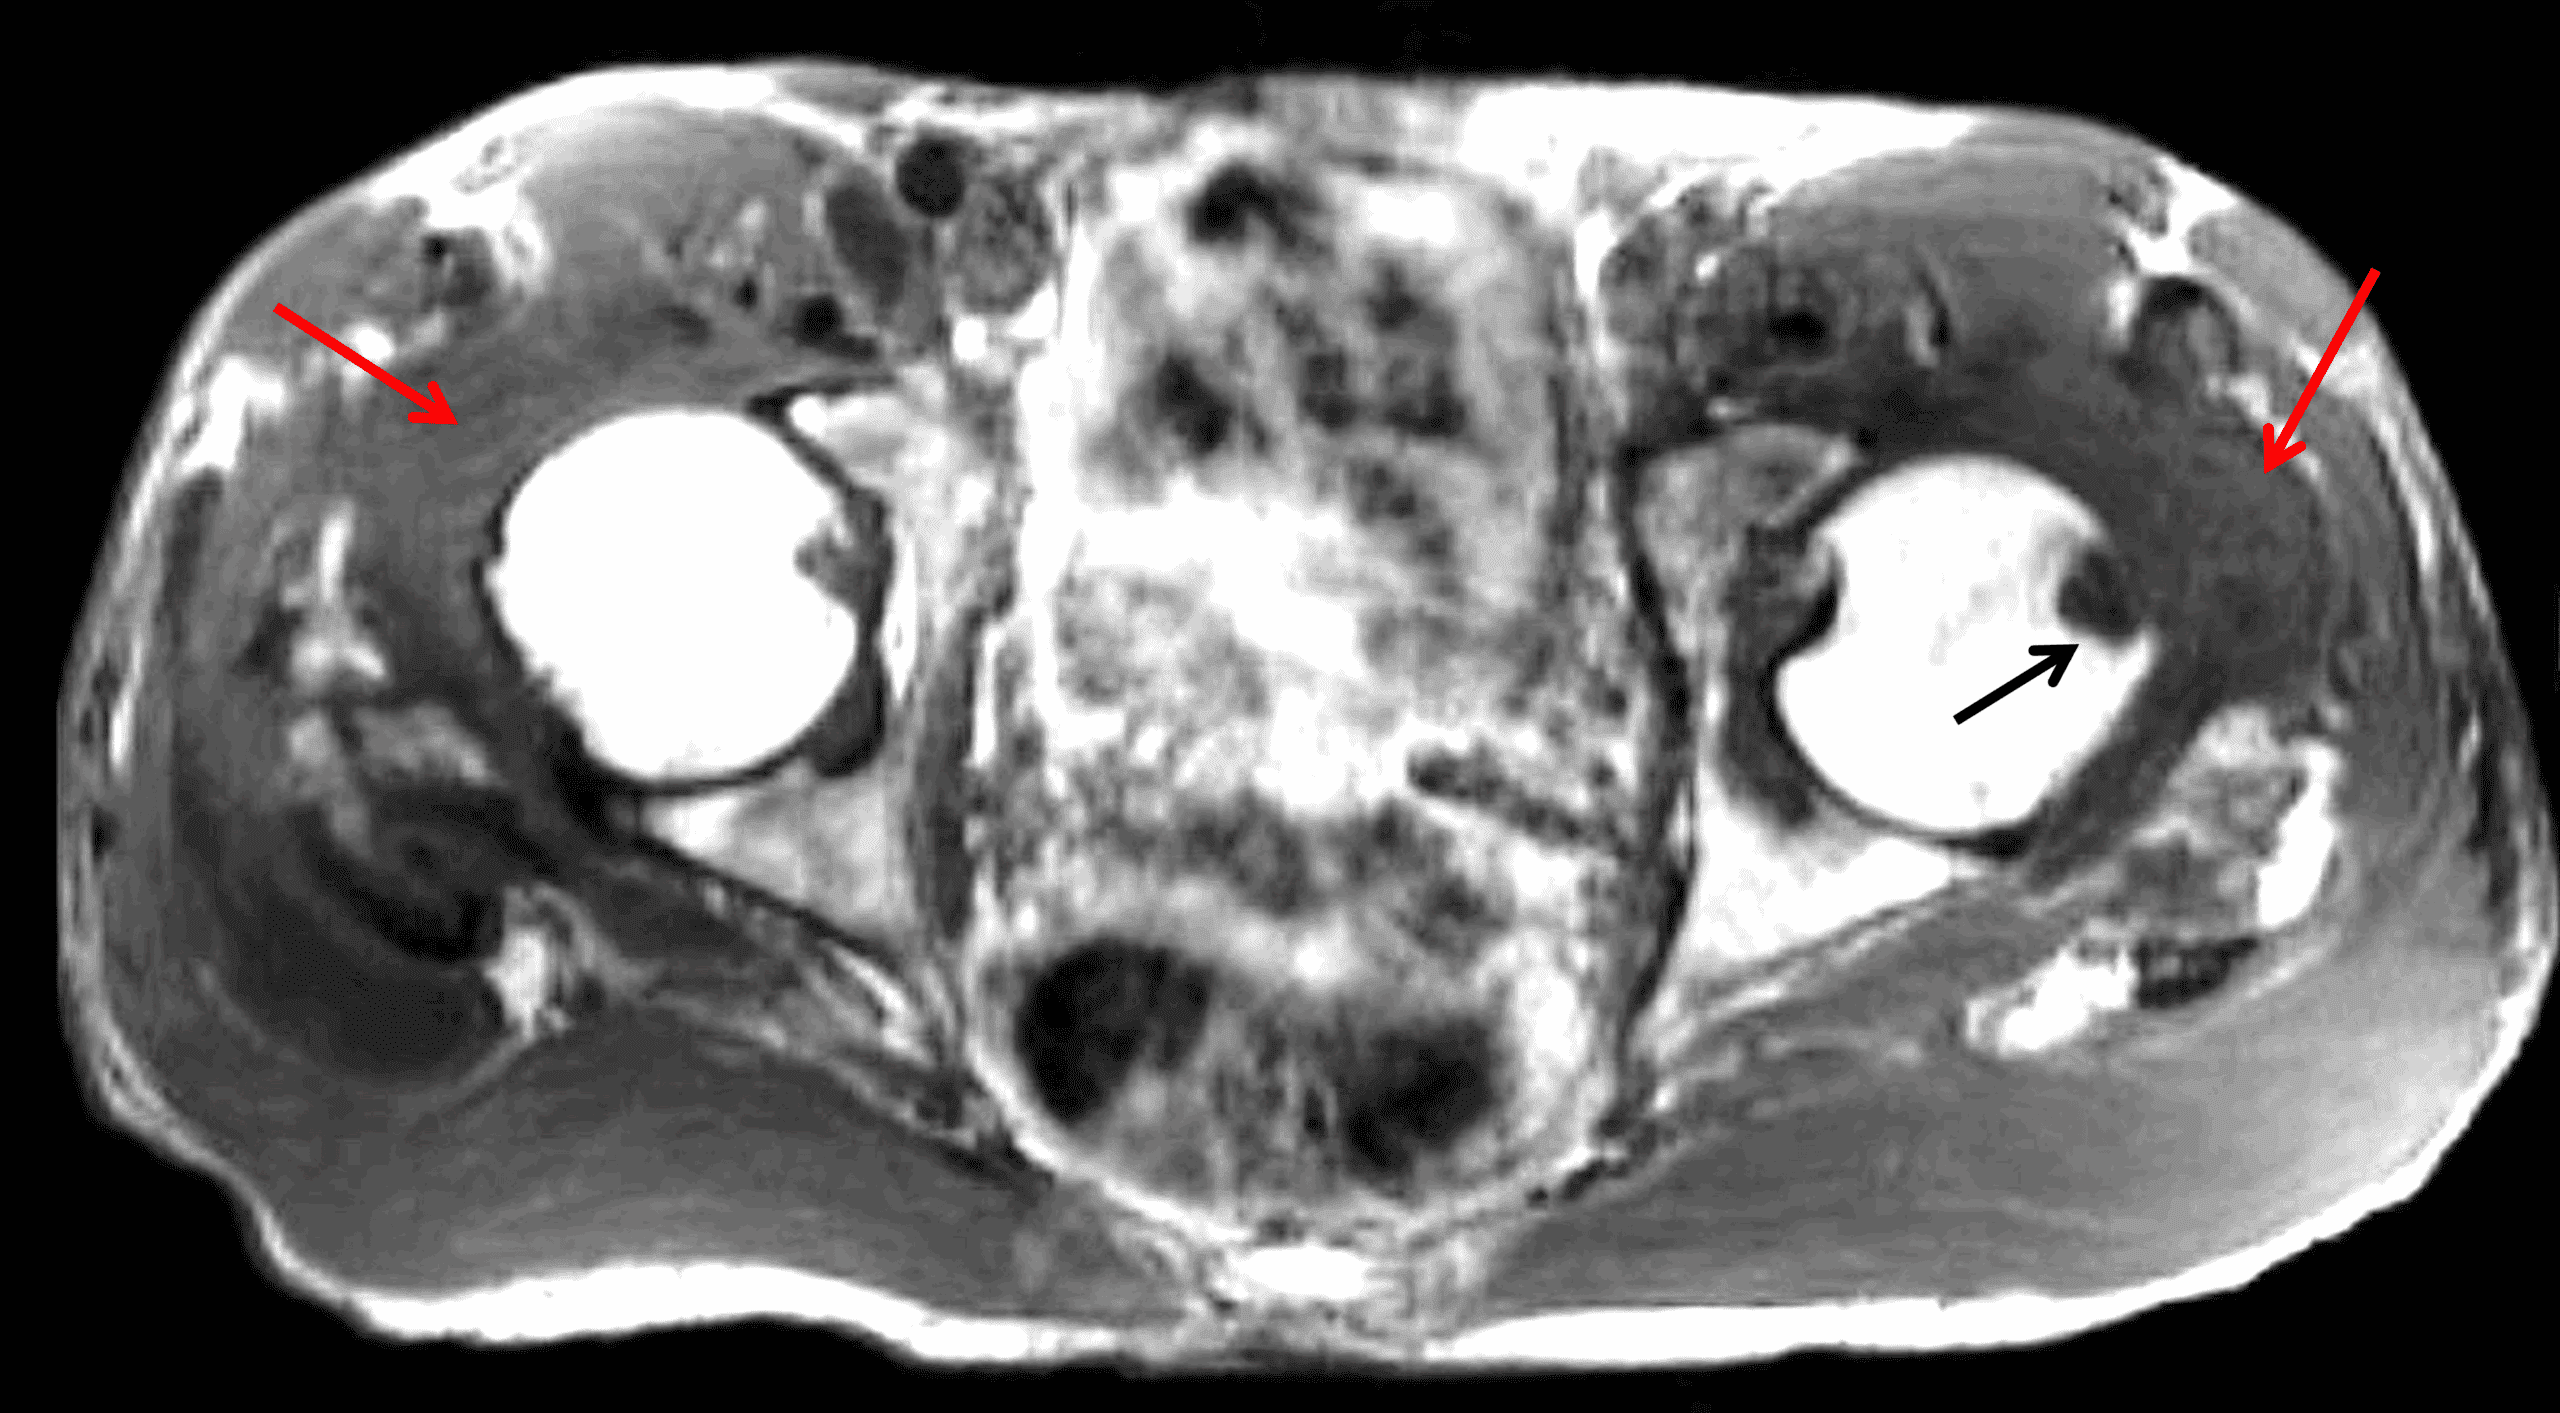

On CT and radiography, juxta-articular soft tissue masses are seen with subchondral cysts, erosions and localized osteopenia as well as joint effusions with preserved joint spaces. On MRI, the masses demonstrate intermediate to hypointense T1 signal, and intermediate T2 signal which can occasionally be variable (Figure 10). Unlike TCGCT, there is usually no hemosiderin or blooming artifact.2-4,18

Figure 10: Amyloidosis in a patient with chronic renal failure. (10A) Axial T1-weighted and (10B) coronal STIR images demonstrate diffuse intermediate to hypointense T1 and heterogeneously intermediate STIR signal masses in both hip joints (red arrows) with an erosion in the left femoral head (black arrow).